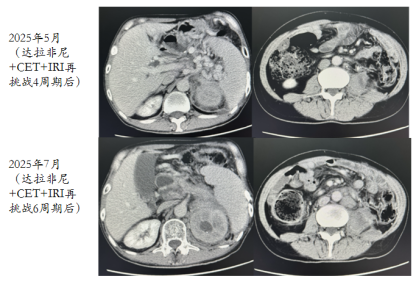

考虑后线治疗有效率低,目前腹痛症状明显,拟行快速缩瘤,与患者及家属商议后,拟再挑战抗BRAF治疗。

2025-03-19开始再挑战达拉非尼+CET+IRI单药治疗。

经过4周期治疗后,患者腹痛及一般情况好转,复查CT评效PR。

image.png

图9 再挑战治疗4周期后复查CT结果

2025-07腰腹痛加重,肿瘤标记物上升趋势。复查CT提示进展。评效PD。

图10 再挑战治疗6周期后复查CT结果